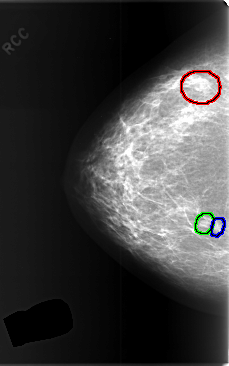

FILE: C_0374_1.RIGHT_CC.OVERLAY

TOTAL_ABNORMALITIES 3

ABNORMALITY 1

LESION_TYPE MASS SHAPE LOBULATED MARGINS CIRCUMSCRIBED

ASSESSMENT 3

SUBTLETY 5

PATHOLOGY BENIGN

TOTAL_OUTLINES 1

BOUNDARY

ABNORMALITY 2

LESION_TYPE MASS SHAPE OVAL MARGINS CIRCUMSCRIBED

ABNORMALITY 3

LESION_TYPE MASS SHAPE ROUND MARGINS CIRCUMSCRIBED